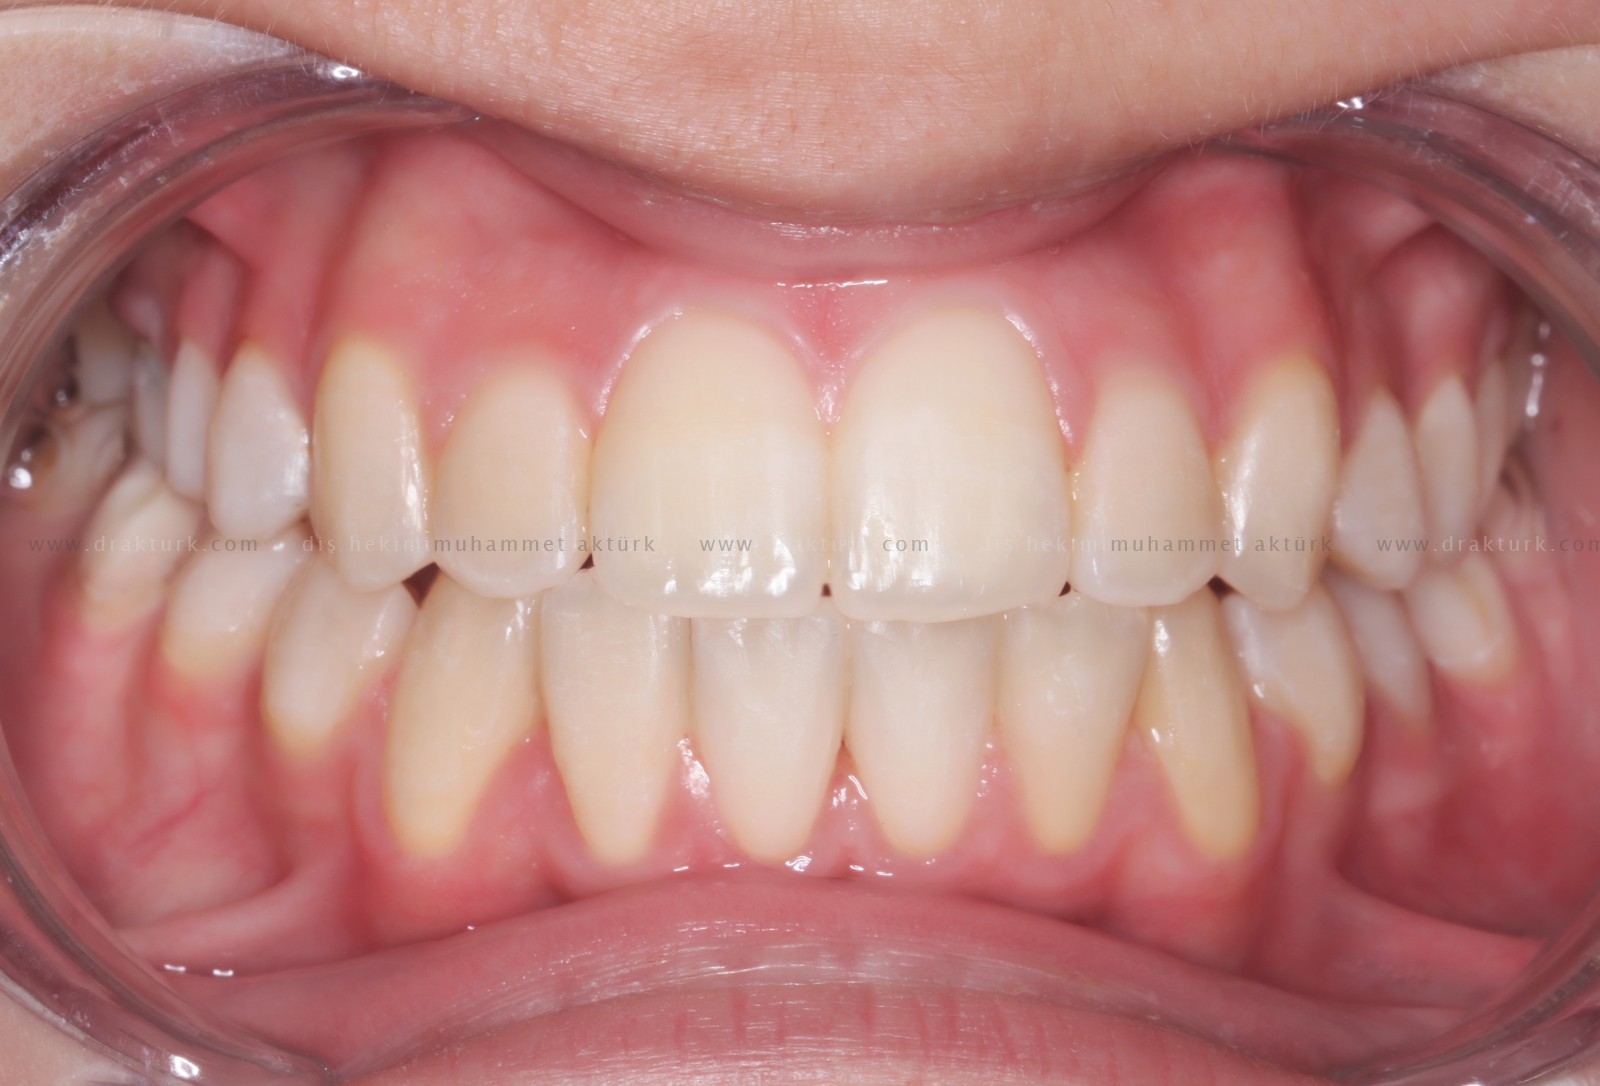

An example of the treatments we have done :

TREATMENT of ANTERIOR TOOTH FRACTURE WITH AESTHETIC COMPOSITE FILLING

After